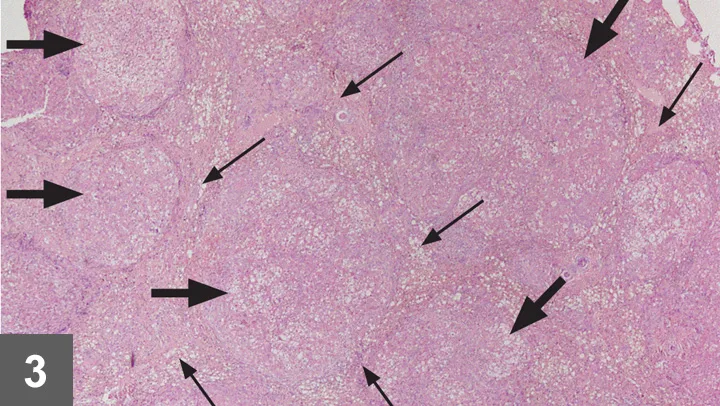

• Liver tissue should be submitted for histopathologic evaluation (Figure 3).

Microscopic view of a tissue sample showing multiple circular structures, likely follicles, surrounded by a pink-stained matrix. Black arrows indicate areas of interest, highlighting cellular features relevant to veterinary pathology.

FIGURE 3 Histopathology sample obtained at laparotomy that demonstrates regenerative nodules (wide arrows) and fibrosis (thin arrows), both of which are indicative of cirrhosis. Hematoxylin and eosin stain; 40× magnification.